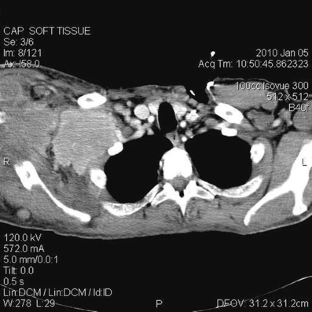

Sikaria, S., Heim-Hall, J., Diaz, E.H. et al. Partial response of a rare malignant metastatic diffuse tenosynovial giant cell tumor with benign histologic features, treated with SCH 717–454, an insulin growth factor receptor inhibitor, in combination with everolimus, an MTOR inhibitor. Targ Oncol 9, 73–79 (2014). https://doi.org/10.1007/s11523-013-0267-8